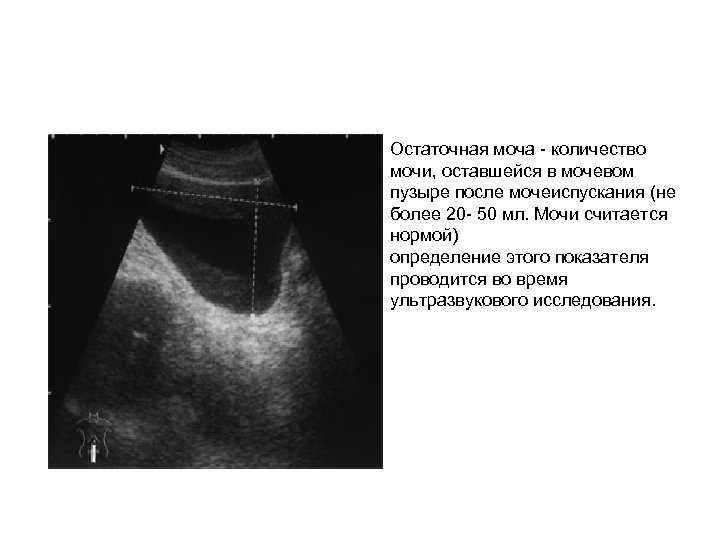

Остаточная моча - количество мочи, оставшейся в мочевом пузыре после мочеиспускания (не более 20 - 50 мл. Мочи считается нормой) определение этого показателя проводится во время ультразвукового исследования.